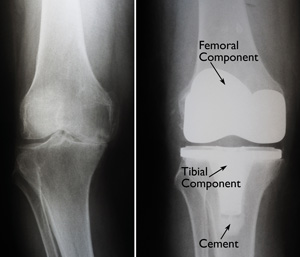

(Left) An x-ray of a severely arthritic knee. (Right) The x-ray appearance of a total knee replacement. Note that the plastic spacer inserted between the components does not show up in an x-ray.